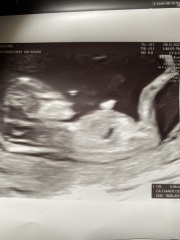

Newtothis5 · 10/02/2017 20:27

Hey all! So when my friends and relatives have been expecting I've loved using 'theories' to guess the gender and quite a lot of the time I have been right. Based on skull and nub theory. We had our scan today and baby is measuring 12 week 5 days. I really wish I had asked for a nub picture as I can't see it on this pic. I think I am swaying more team blue. What do you all think? :)

Skull theory